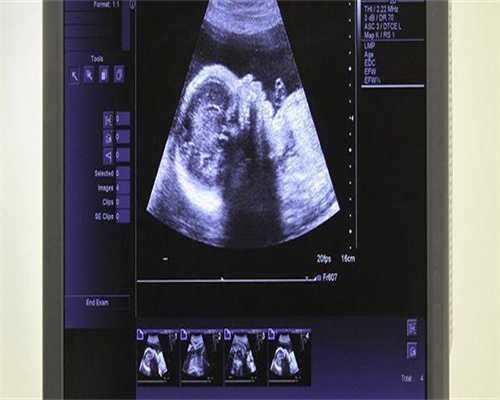

试管婴儿技术是一种辅助生殖方法,可以帮助因卵巢问题等原因而无法自然受孕的夫妇。在试管婴儿技术中,卵子和精子在实验室中结合形成胚胎,然后将胚胎植入母亲的子宫内实现怀孕。

试管婴儿技术的成功率受多种因素的影响,包括女性的年龄、卵子的质量、子宫内膜的健康状况以及男性精子的质量。对于卵巢粘连的患者来说,试管婴儿可能是一个有效的选择,因为它不需要正常的排卵过程。一些医疗机构,如广州协和医院和山东大学齐鲁医院,提供优质的试管babies 服务。